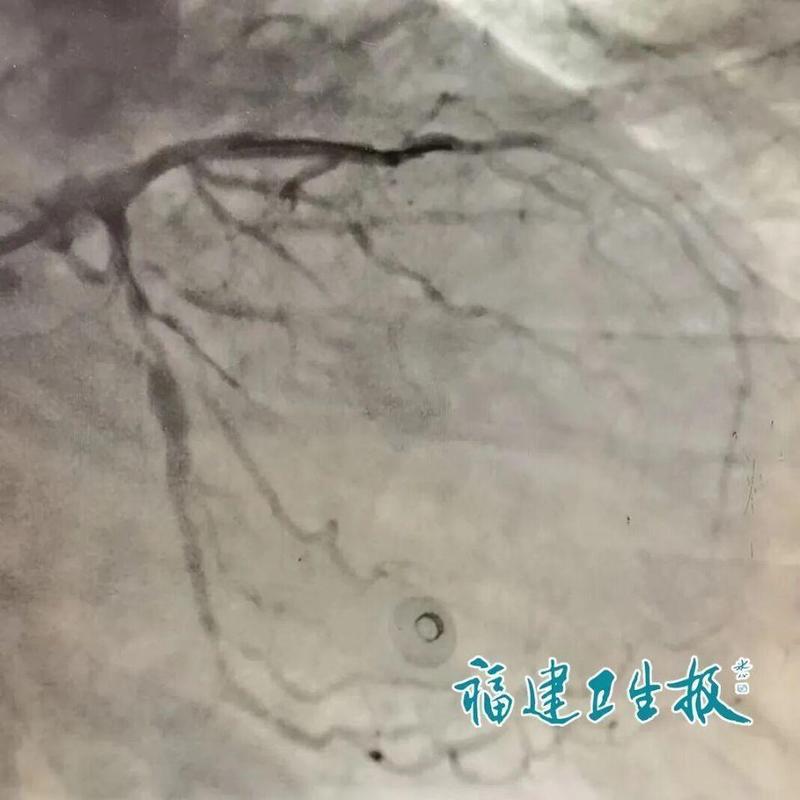

从专业的视角审视,叶大爷的坚持实际上是一场豪赌。心电图上那典型的“墓碑样”改变,预示着心脏血管已近乎完全闭塞,心肌坏死在分秒间推进。此时的“回乡治疗”并非简单的行程选择,而是将心脏置于极度不稳定的环境中,数小时的高铁与大巴颠簸,对于一个随时可能发生心源性休克的患者而言,无异于在死神手中抢时间,且胜算极低。